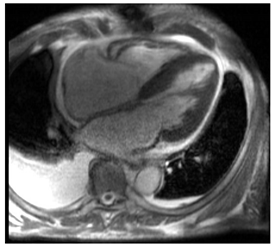

CMR can help differentiate amyloid CM from other infiltrative or hypertrophic cardiomyopathies. It is a complementary diagnostic tool to serological workup, bone scintigraphy, and endomyocardial biopsy. CMR can also offer prognostic and disease-monitoring ability. Cine steady-state free precession (SSFP) sequences examine the morphology and function of the four cardiac chambers. Like echocardiography, SSFP in amyloid CM shows increased LV wall thickness, atrial septal thickness, and valvular thickness with normal or reduced biventricular function. LV septal hypertrophy is mostly asymmetric in ATTR-CM and concentric in the majority of AL-CM [].

Post-contrast CMR imaging provides information about the extracellular space, which in amyloid CM is distorted by amyloid deposition. In amyloid CM, TI-scout images for gadolinium kinetics show a simultaneous nulling of the blood pool and myocardium or a reverse null pattern where the myocardium nulls prior to the blood pool []. LGE patterns in amyloid CM range from absence to subendocardial or transmural, correlating with the severity of infiltration. LGE often involves all cardiac chambers. Contrast-enhanced T1-weighted imaging can be used to estimate extracellular volume (ECV), which is often markedly increased in amyloid CM (>40%) due to extracellular amyloid deposition []. Elevated ECV was shown to precede LGE in certain cases with a high probability of amyloid CM, likely signaling early disease []. However, the use of Gd to evaluate LGE and ECV may be precluded in patients with advanced kidney disease. Other contrast-free analyses of CMR that can help distinguish amyloid CM include longitudinal strain analysis. Similar to echocardiography, CMR shows globally reduced longitudinal strain in amyloid CM with relative apical sparing with specificity to distinguish CA of 82% but sensitivity of only 43% []. If Gd can be administered, the LGE ratio between base and apex, in addition to the relative strain ratio, was shown to have a higher discriminatory ability to distinguish amyloid CM from other causes of LVH []. Key CMR findings in amyloid CM are summarized in Table 1.